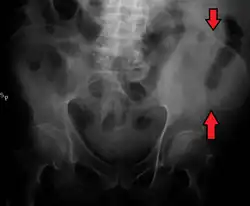

![]() Pelvic girdle. | |

The crest of the ilium (or iliac crest) is the superior border of the wing of ilium and the superolateral margin of the greater pelvis.

The iliac crest stretches posteriorly from the anterior superior iliac spine (ASIS) to the posterior superior iliac spine (PSIS). Behind the ASIS, it divides into an outer and inner lip separated by the intermediate zone. The outer lip bulges laterally into the iliac tubercle.[1] Palpable in its entire length, the crest is convex superiorly but is sinuously curved, being concave inward in front, concave outward behind.[2]

It is thinner at the center than at the extremities.

The top of the iliac crests also marks the level of the fourth lumbar vertebral body (L4), above or below which lumbar puncture may be performed. Furthermore, said level is often referred to as the "intercristal line".